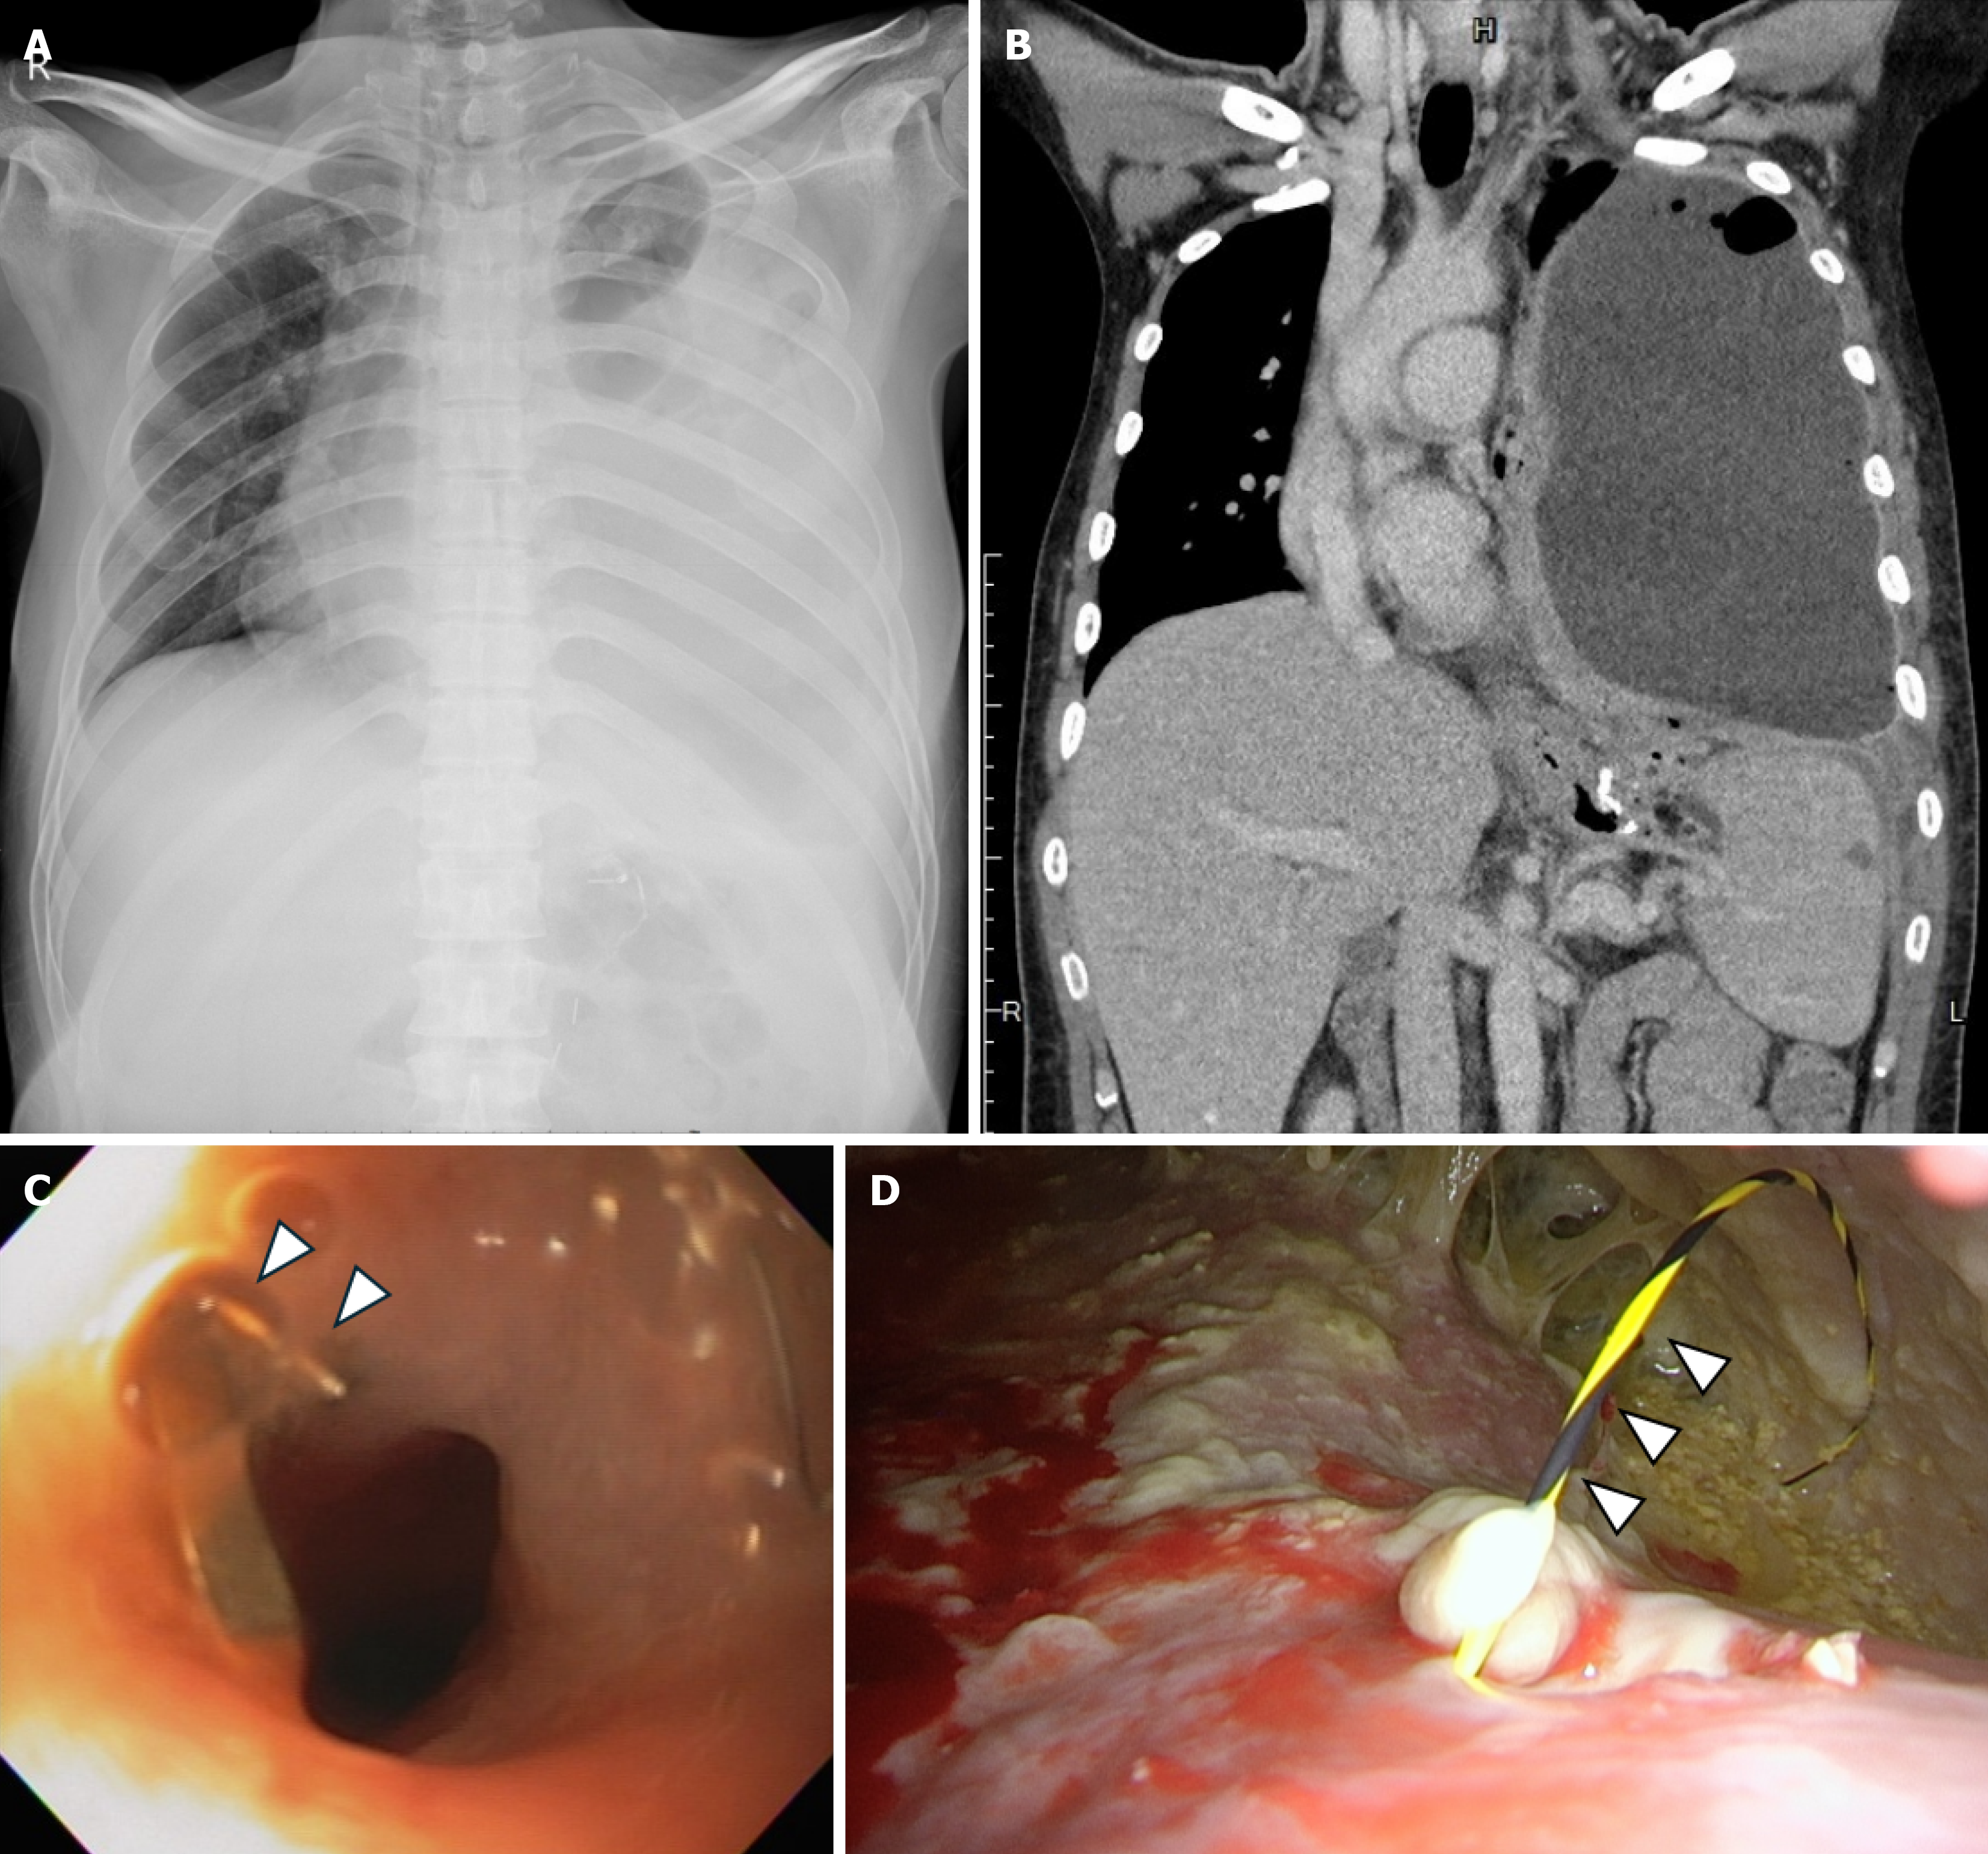

Figure 1 Imaging at presentation.

A: Chest X-ray revealed a left-sided pleural effusion; B: Computed tomography showed a hydropneumothorax; C: Esophagogastroduodenoscopy identified a fistula with purulent discharge near the staple line (arrow heads) of the sleeved stomach; D: Thoracoscopic view of a guidewire (arrow heads) passing from the fistula through the diaphragm into the pleural cavity.